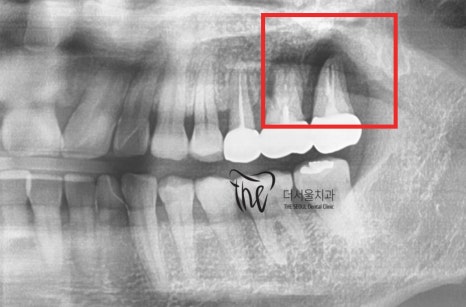

사진에서 볼 수 있듯이, 크라운 하방의

cervical line 경계면쪽에 잇몸이 퇴축이

되어있는 것을 볼 수 있습니다.

이는, 뼈도 같이 퇴축이 되었다는 것을 뜻하는데

엑스레이로 보니 치아 뿌리 끝에

염증이 발생 되어있는 것을 볼 수 있습니다.

이러한 apical lesion 의 범위가 크기 때문에

염증치료를 하더라도 사실 크게 의미가 없습니다.

그러면서, 손으로 만졌을 때에

Mobility(흔들림)도 같이 느낄 수 있었습니다.

즉, 발치를 할 수 밖에 없는 상황이라는겁니다.